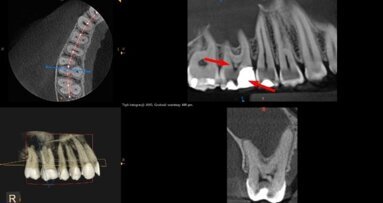

W artykule przedstawiono sposób wykorzystania CBCT jako badania umożliwiającego nie tylko dokładną diagnostykę, ale również planowanie ...